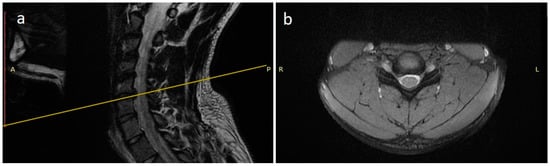

A 21 years-old male professional judoka started to feel neck pain radiating in the right C6 root dermatome with weakness in flexion-extension of the right forearm during a training activity. Due to the worsening of symptoms, the patient was suspended from the practice of judo. Moreover, he underwent a cervical spine MRI that showed the presence of C5-C6 disc herniation with C6 root compression and without spinal cord compression (Figure 2). After three months of conservative treatment (NSAIDs, steroids, physical therapy), surgical treatment was proposed. A standard C5-C6 ACDF with intraoperative neuromonitoring was performed with implantation of a stand-alone PEEK cage (CoRoent Small Interlock, NuVasive, San Diego, CA, USA) anchored with three titanium screws and packed with a biphasic calcium-phosphate bone graft substitute (AttraX Putty, NuVasive Inc., San Diego, CA, USA). The surgery was followed by a sudden relief from radicular pain, and the patient was discharged in two days. After a month of recovery, no motor or sensory deficits were detected at a neurosurgical follow-up visit. The CT of the cervical spine, three months after surgery, showed bone bridging as an initial sign of arthrodesis (Figure 3). In consideration of clinical and radiological outcomes, we recommended returning to training after 6 months and returning to competitive activities 7 months after surgery.

Figure 2.

MRI scan sagittal (a) and coronal (b) images of the cervical spine showing a C5-C6 disc herniation with C6 root compression.